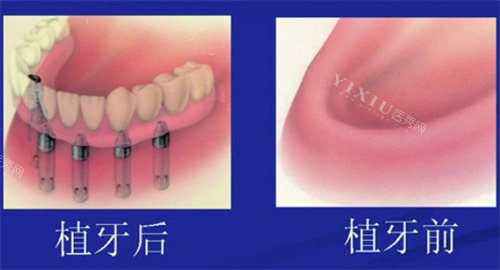

全口种植牙

全口种植牙是指上下颌牙齿全部缺失后,通过植入人工牙根(种植体)来支撑固定全口义齿的修复方式。通常需要在上颌或下颌植入4-8颗种植体,然后在其上安装固定或可拆卸的义齿。

半口种植牙是指上颌或下颌其中一侧牙齿全部缺失后进行的种植修复。与全口种植类似,但只需要修复半口牙齿,所需种植体数量相对较少。